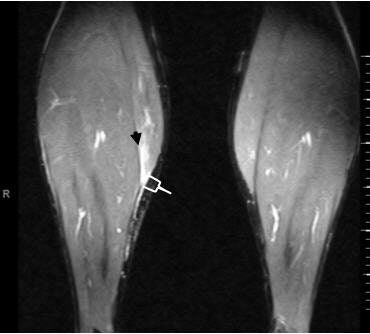

A 35-year-old male with a partial rupture of the medial head of the gastrocnemius at the musculotendinous junction. Top, the longitudinal US image shows the medial head of the gastrocnemius muscle with partial discontinuity of the muscle fibers (double arrows). A small hypoechoic fluid collection (single arrow) is noted. G = gastrocnemius muscle, S = soleus muscle. Below, the longitudinal US image one week later shows a hyperechoic fluid collection (arrows). This fluid can be considered as most likely representing flesh blood.